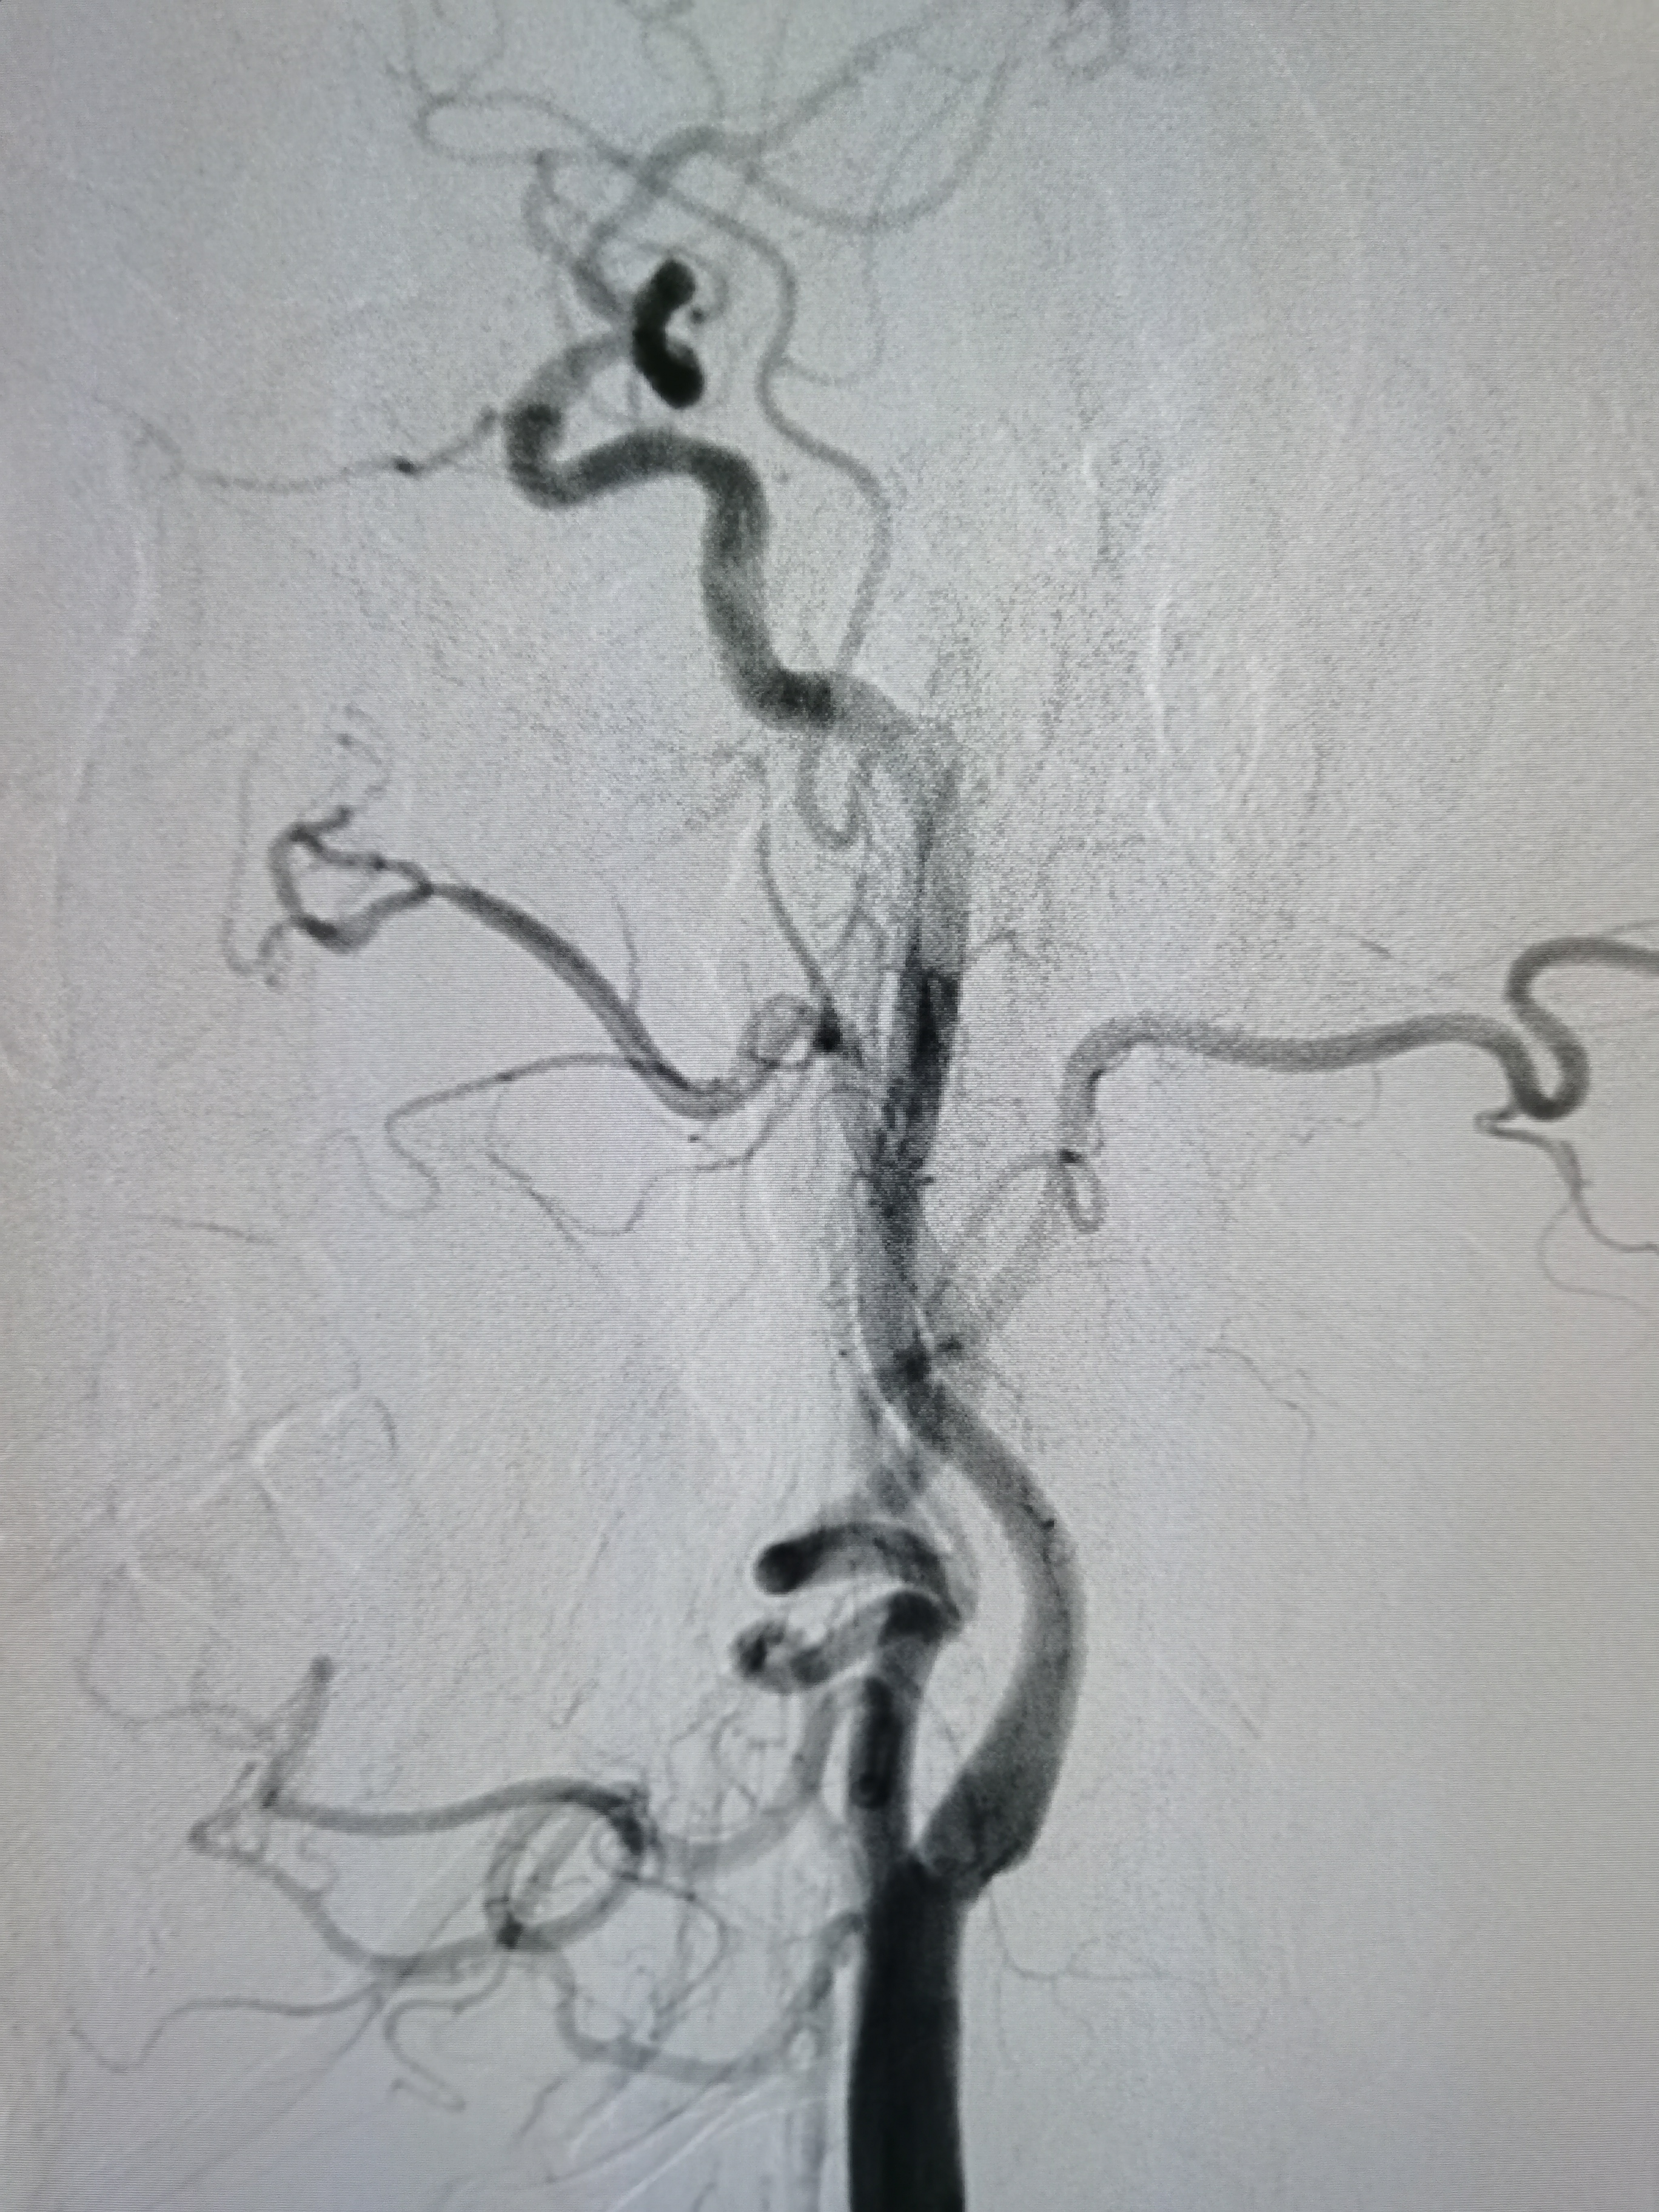

左侧颈内动脉起始部正常。

左侧大脑前动脉发育不良。

左侧大脑中动脉显影正常。

右椎动脉劣势。

颅内血流可。

左椎动脉优势。

基底动脉显影正常。